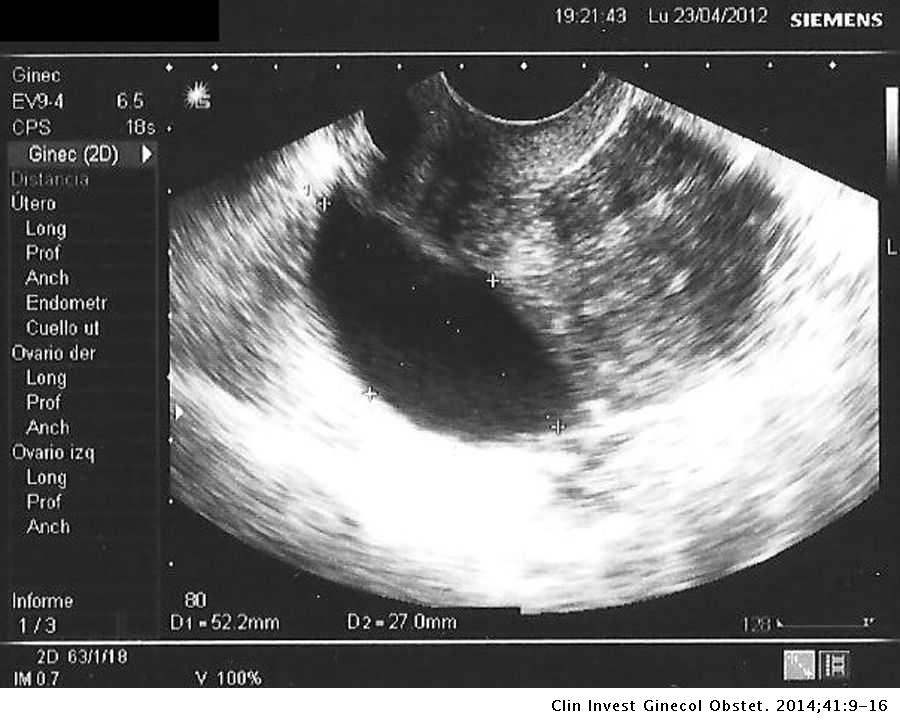

Dispositivo Intrauterino Liberador De Levonorgestrel Diu Mirena Y Quistes De Ovario Clinica E Investigacion En Ginecologia Y Obstetricia